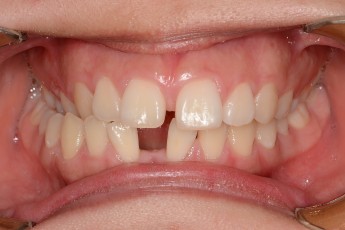

BEFORE & AFTER

- 덧니교정